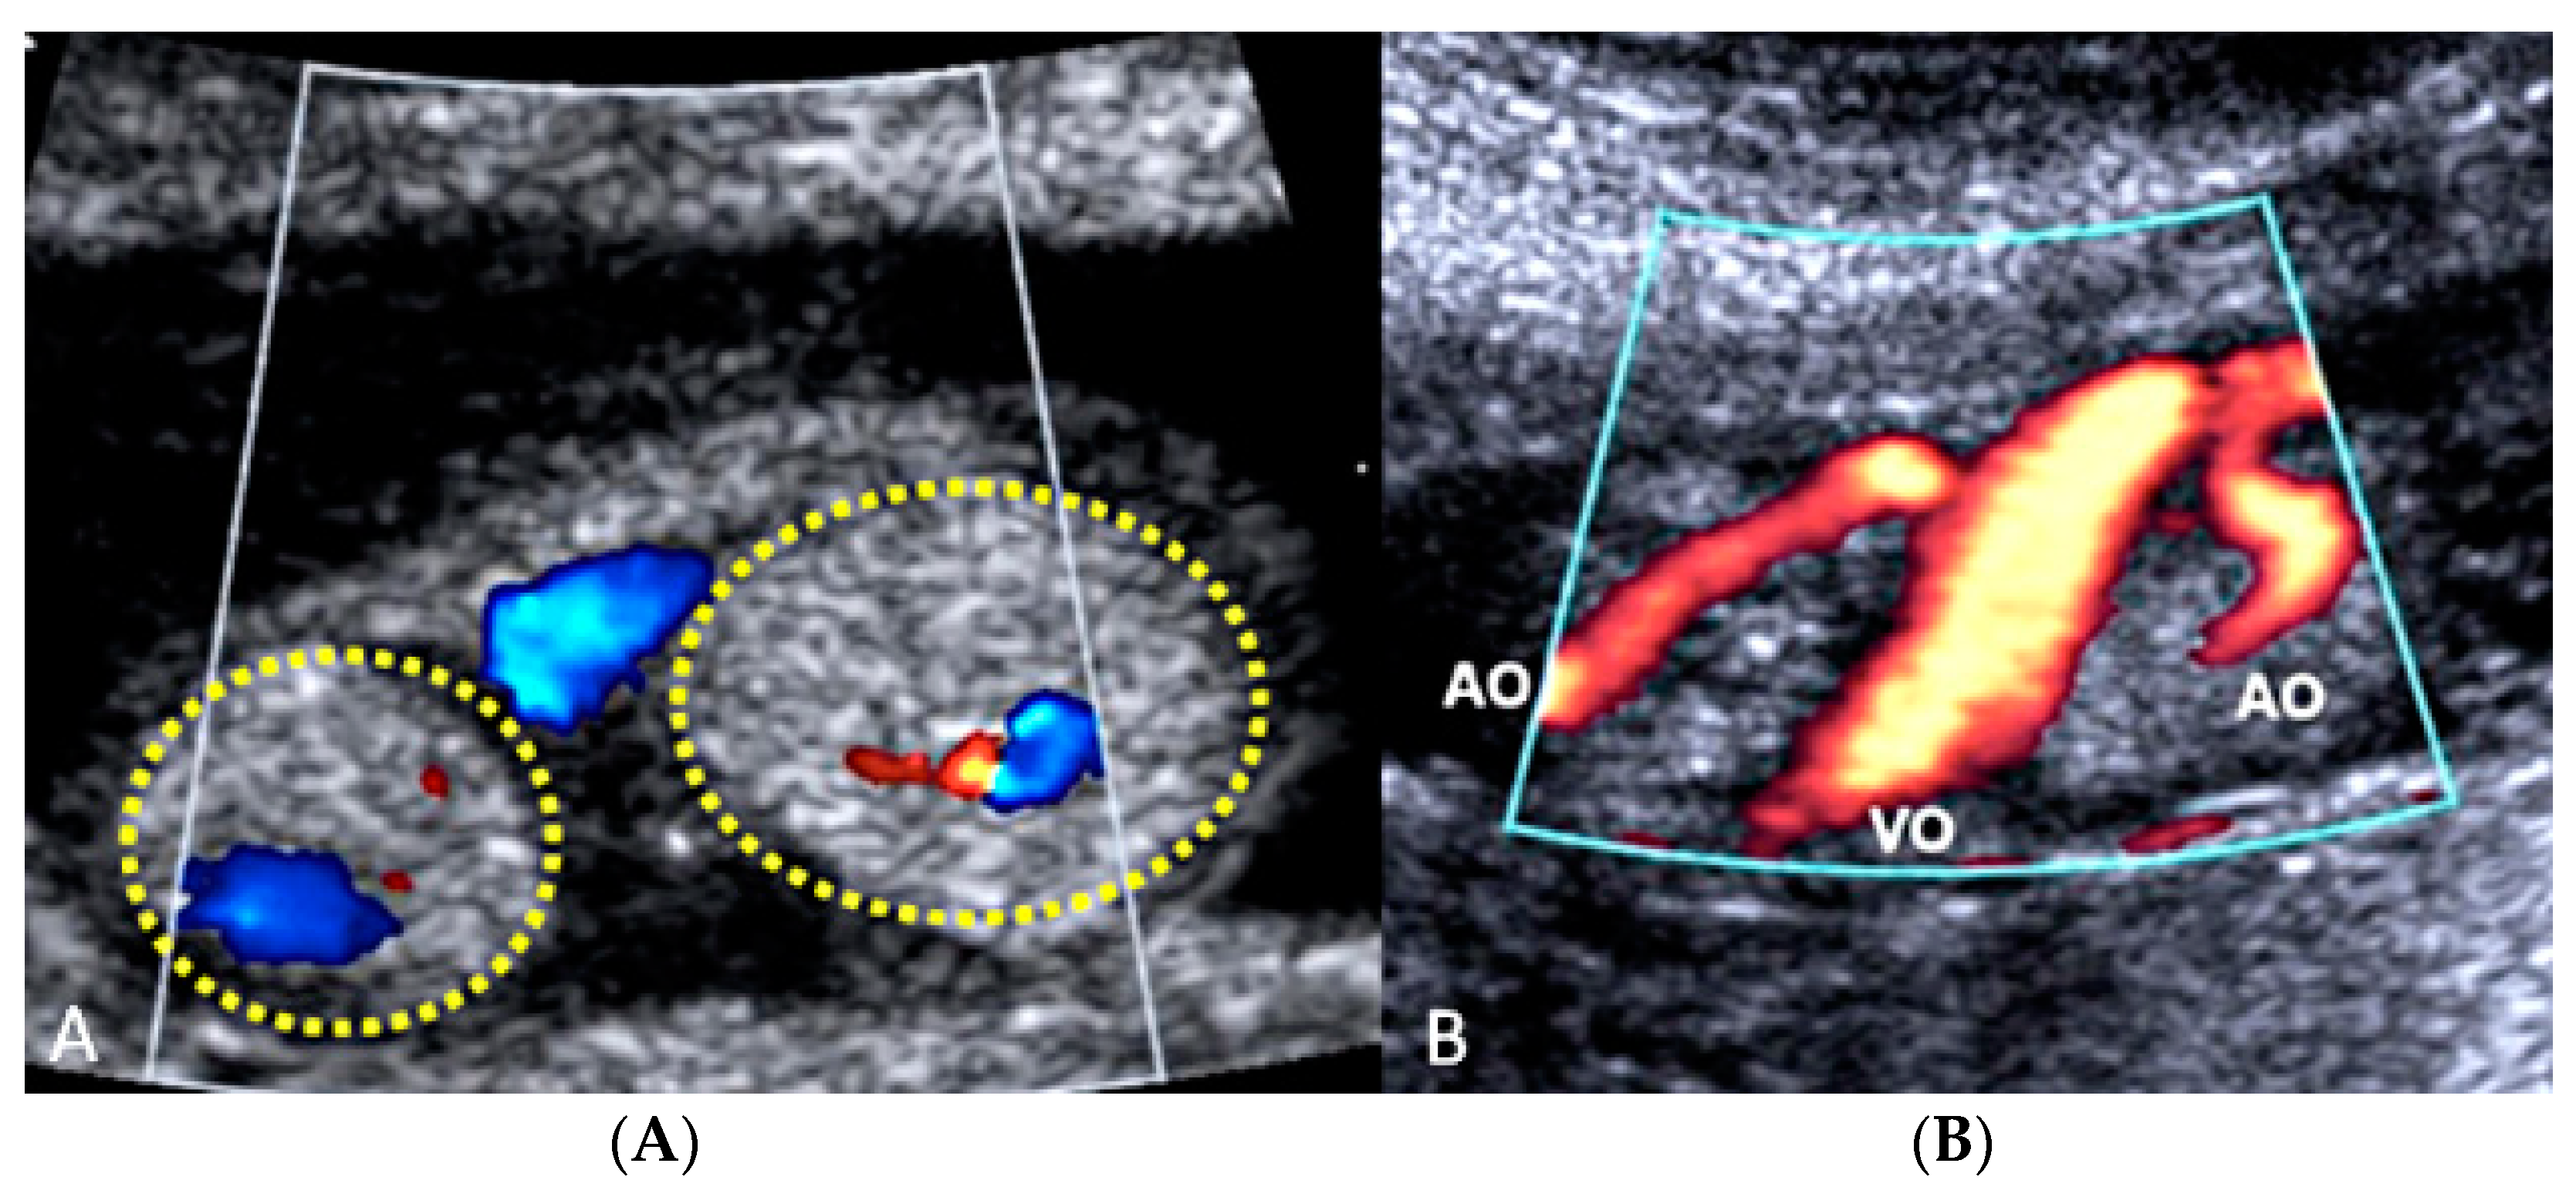

3.2.7. Umbilical Cord Hemangioma

Umbilical cord hemangioma is the most frequently reported cord tumor and is usually located at the placental insertion site [47]. It has been associated with congenital anomalies and increased perinatal mortality [62], mainly due to impaired umbilical circulation owing to tumor proliferation, vascular compression, intravascular thrombosis or fetal hemorrhage due to ruptured vessels [63]. Sonographic evaluation shows a hyperechogenic mass within the umbilical cord, which may also appear edematous, and it has differential diagnosis with hematomas and teratomas, placental masses and abdominal wall defects [62,63] (Figure 26 and Figure 27).

Figure 26.

Sonographic evaluation of umbilical cord hemangioma. (Legend: AO: umbilical artery; VO: umbilical vein). Umbilical cord hemangioma or angiomyxoma is usually located in the terminal portion of the cord on the placental side. Two-dimensional color (A) and power Doppler ultrasound (B) may detect a fusiform or saccular swelling of the umbilical cord. Umbilical arteries are surrounded by a particularly echogenic material arranged as a sheath of the same vessels. The mechanical compression of the umbilical circulation may be determined by an enlargement of the mass and stenosis of the umbilical vessels also caused by the intraluminal proliferation of the hemangioma. Blood flow reduction can be abruptly compromised through the twisting of the cord favored by the mass and by the presence of pseudocysts. An accurate follow-up is mandatory.